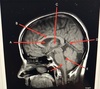

Match 1. Lentiform nucleus 2. 3rd ventricle 3. Caudate nucleus 4. Frontal sinus 5. Thalamus

A. Caudate nucleus B. Thalamus C. 3rd ventricle D. Lentiform nucleus E. Frontal sinus